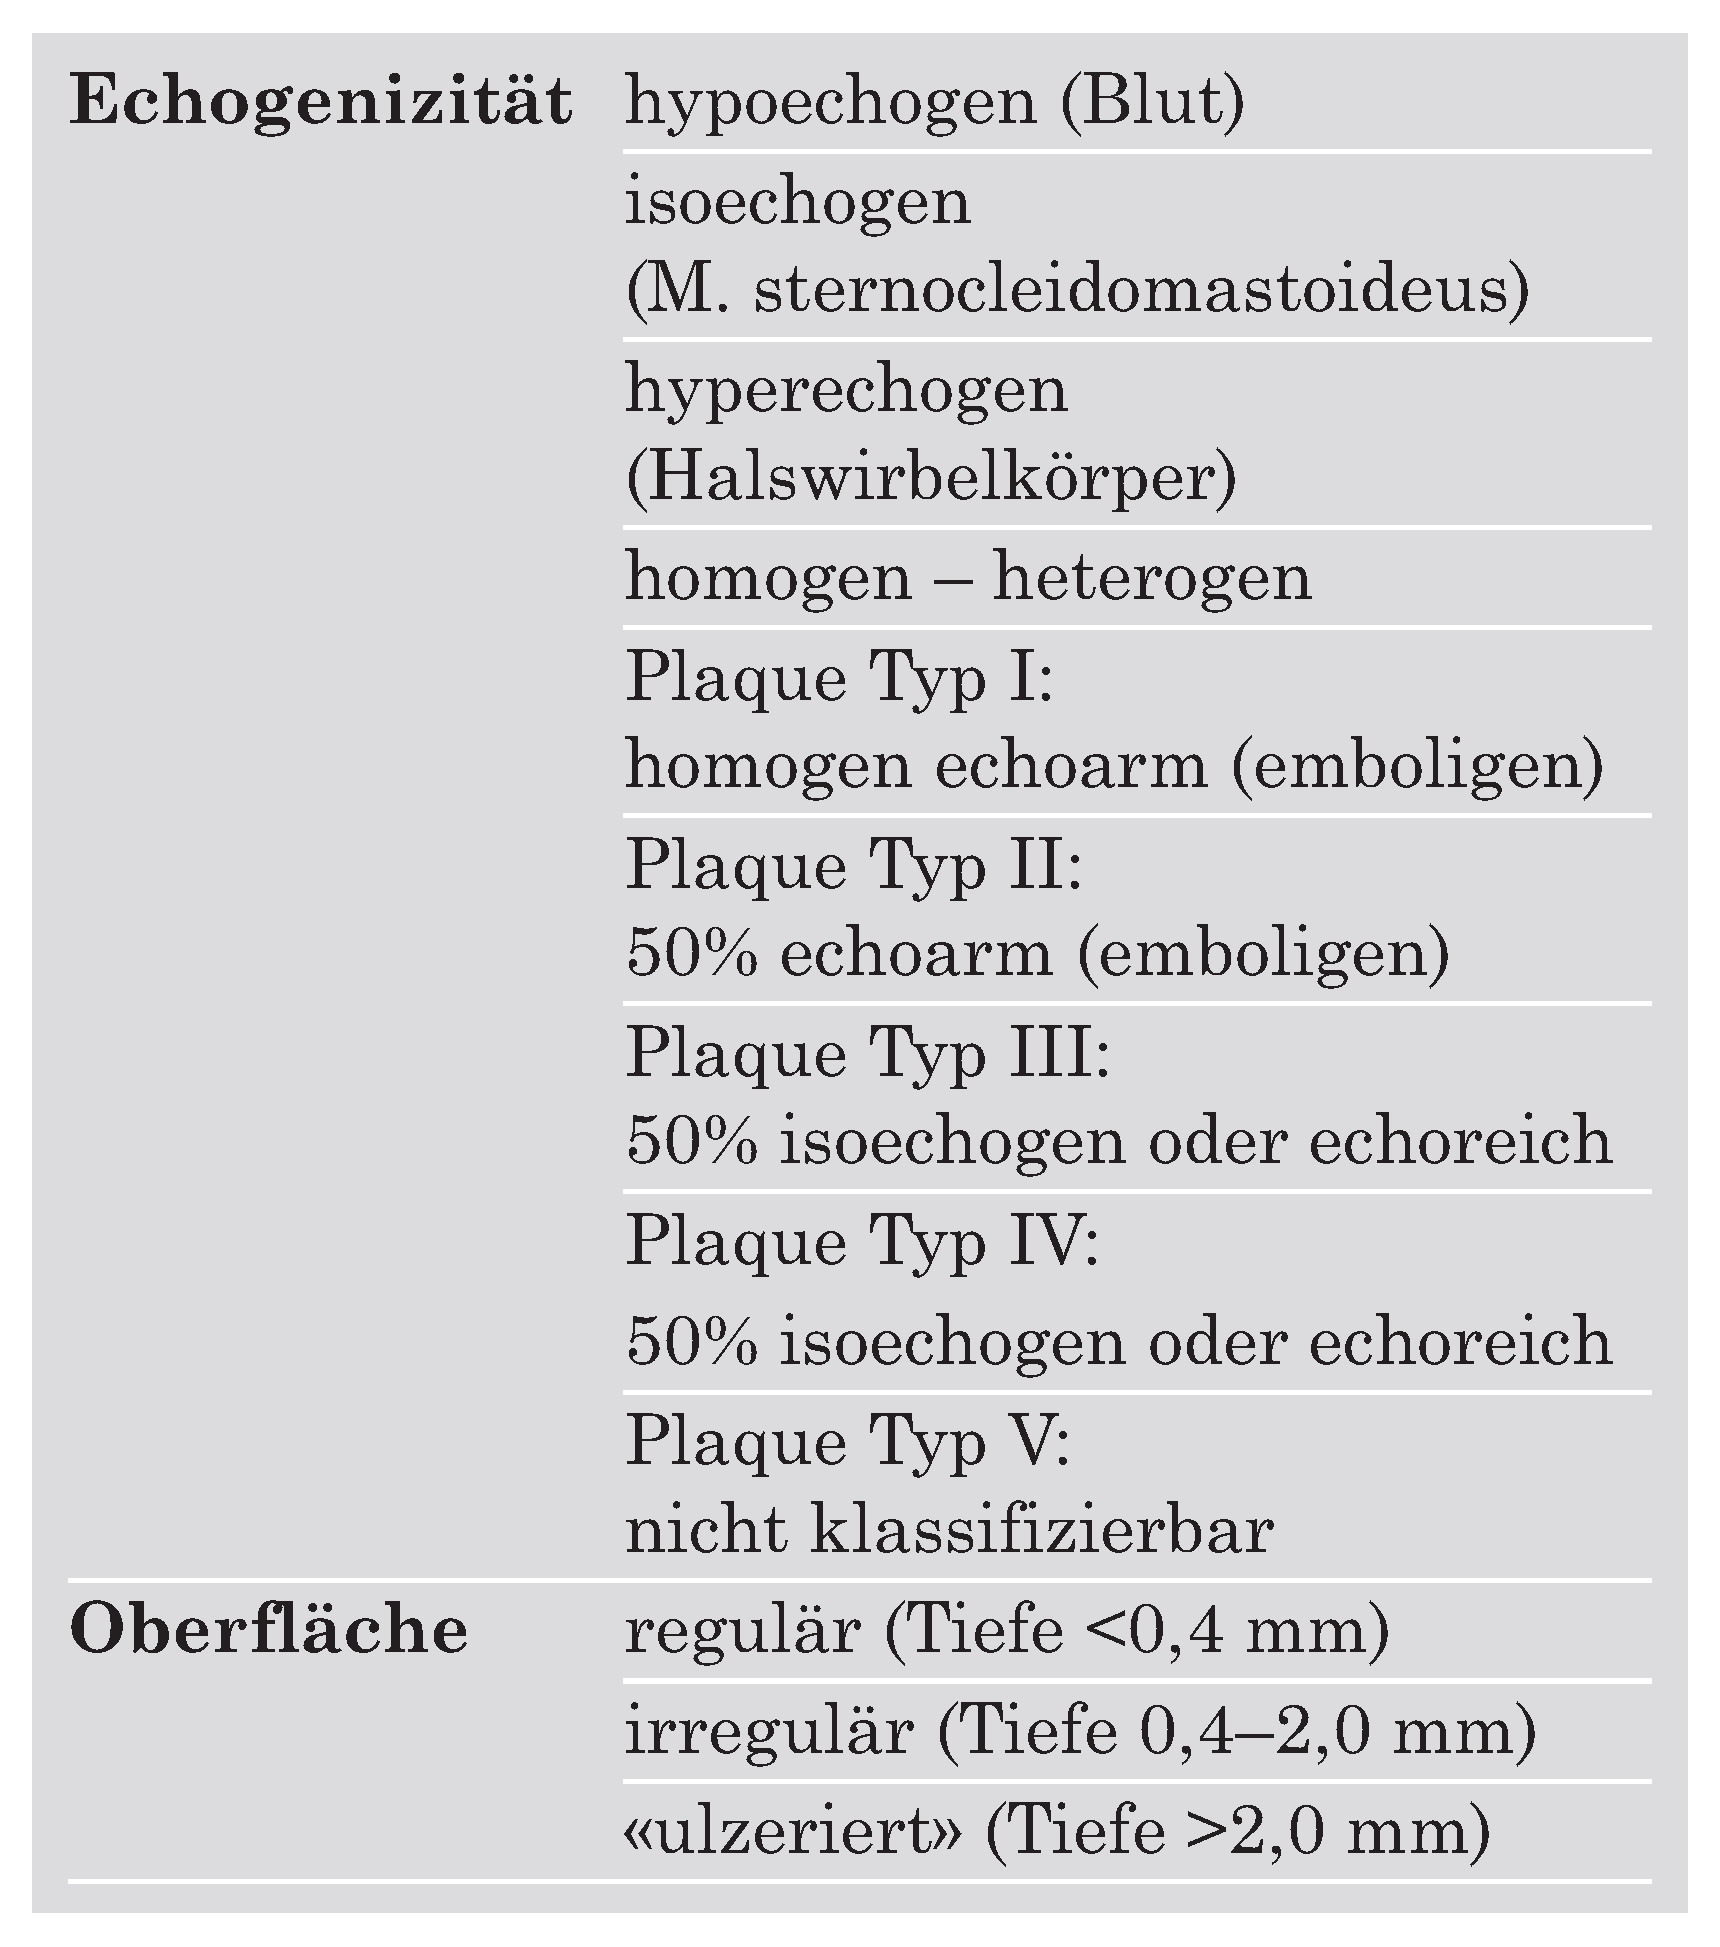

Ultrasonographische Verfahren